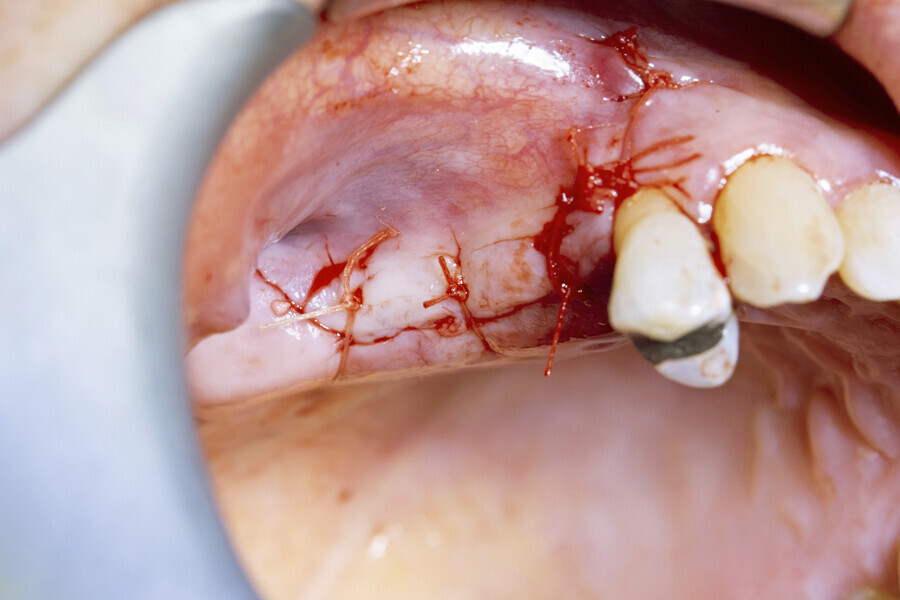

Next, the large quantity of autogenous bone collected with the disposable BoneTrap (Dentsply Sirona) during surgery was used to augment the small bone fenestration (Figs. 6 & 7), and Symbios Xenograft Granules were layered over the autogenous bone (Fig. 8). Finally, Symbios Collagen Membrane SR (15 × 20 mm) was trimmed to shape to complete the guided bone regeneration procedure (Fig. 9). The wound was closed with PGA sutures (Fig. 10), and radiographic evaluation was performed to verify the implants postoperatively (Fig. 11). Three months later, medium Healing Abutments EV were placed (Fig. 12).

Fig. 10: Passive primary closure with PGA sutures.